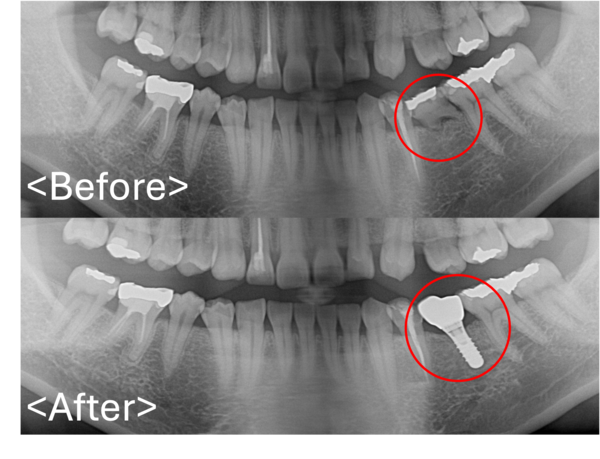

ビフォーアフター画像|【症例】歯根破折を起こし抜歯になった奥歯の標準的なインプラント治療|港南台の歯医者 港南台パーク歯科クリニック

患者様と歯がなくなってしまった部位について、今後どのような方法で歯を入れていくかを相談しました。   治療法①:部分入れ歯(治療は簡単ではありますが、1番違和感が強い治療になりま...